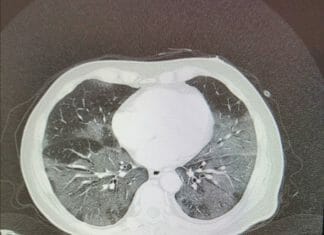

Việc thiếu giường trầm trọng và các thể loại drama kèm theo bắt đầu kéo tới. Từng khoảng trống trong bệnh viện được lấp đầy bởi các con bệnh với tốc độ kinh hoàng. Các bảng hiển thị với tên của bệnh nhân, với các màu khác nhau tùy thuộc vào đơn vị phẫu thuật, giờ đây đều có màu đỏ và thay vì phẫu thuật có chẩn đoán, luôn luôn giống nhau: viêm phổi kẽ hai bên.

Xin hỏi các vị có loại cúm nào mang đến thảm kịch kinh dị như vậy??? Tôi sẽ nói sự khác biệt giữa Covid và cúm (bây giờ tôi sẽ nói kĩ thuật một chút): Với cúm thường, ngoài việc lây lan rất là chậm, những trường hợp biến chứng rất là hiếm. Chỉ khi con VIRUS phá huỷ các hệ thống bảo vệ hệ hô hấp trong cơ thể chúng ta, để những VI KHUẨN vẫn thường trú tự nhiên ở thực quản. Người trẻ thì đỡ chứ người già thì xác định. Covid 19 nguy hiểm hơn SARS ở chỗ nó tấn công thẳng vào các túi phổi, lây nhiễm làm vô hiệu hoá chức năng của túi phổi. Thường thì bệnh nhân nhập viện vài ngày là bắt đầu suy hô hấp nặng, những bình oxy thường được để sẵn trong phòng bệnh không thể đủ.